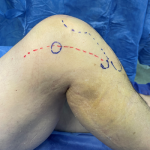

INSTRUCCIÓN ORTOPÉDICA DE POSGRADO – IMÁGENES

499

Presentación del caso

Bibiana Dello Russo, Mónica Galeano, Florencia D´Adamo

604

Resolución del caso